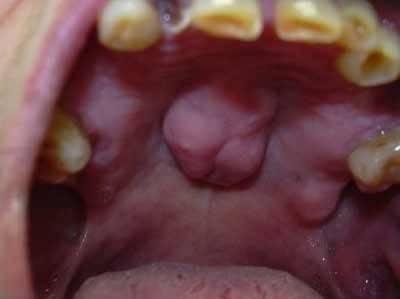

Lo studio dentistico del Dott. Peroni è situato a Flero in provincia di Brescia in via Vittorio Emanuele II, 49. Il Dott. Peroni è specializzato nella medicina chirurgica dentale ed odontoiatrica ed offre i seguenti servizi: Diagnostica, Igiene orale professionale, Restaurativa e Conservativa, Endodonzia, Chirurgia orale, Implantologia, Patologia orale, Ortodonzia, Posturologia, Analgesia Sedativa, Gnatologia, Pedodonzia e Protesi. Presso gli Studi Dentistici del Dottor Peroni ci prendiamo cura dei vostri denti e restauriamo il corretto stato delle vostre bocche. Per fissare un appuntamento con il Dottor Peroni o con i suoi collaboratori è possibile chiamare lo 030 2761577 o scrivere una mail a info@dentistaperoni.it.

Keywords ortognatodonzia, gnatologia, ortodonzia estetica, ortodonzia per bambini, pedodonzia, endodonzia, ortodonzia invisibile, ortodonzia chirurgica, trattamenti di igiene orale, patologia orale, igienisti dentali, sbiancamento denti, pronto soccorso dentistico, chirurgia dentistica, implantologia dentale, dentisti medici chirurghi ed odontoiatri, protesi fisse su denti naturali, analgesia sedativa, endodonzia conservativa, ortodonzia posturale.